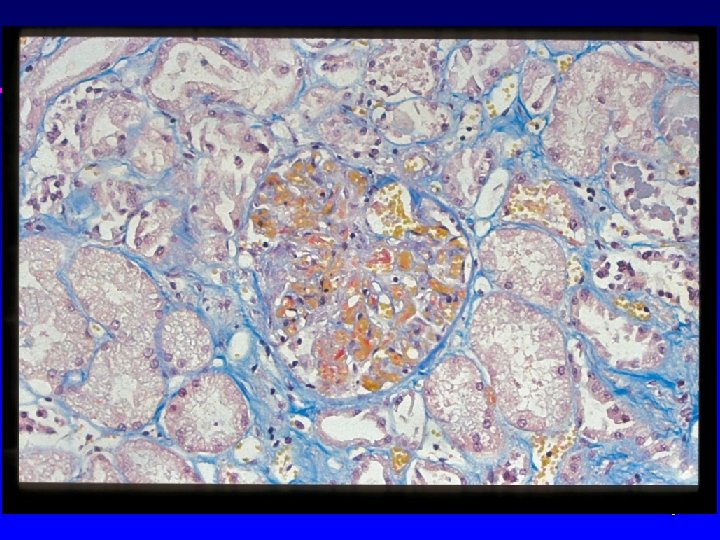

Pulmonary artery – intimal fibrosis

Plexiform lesion – primary pulmonary hypertension